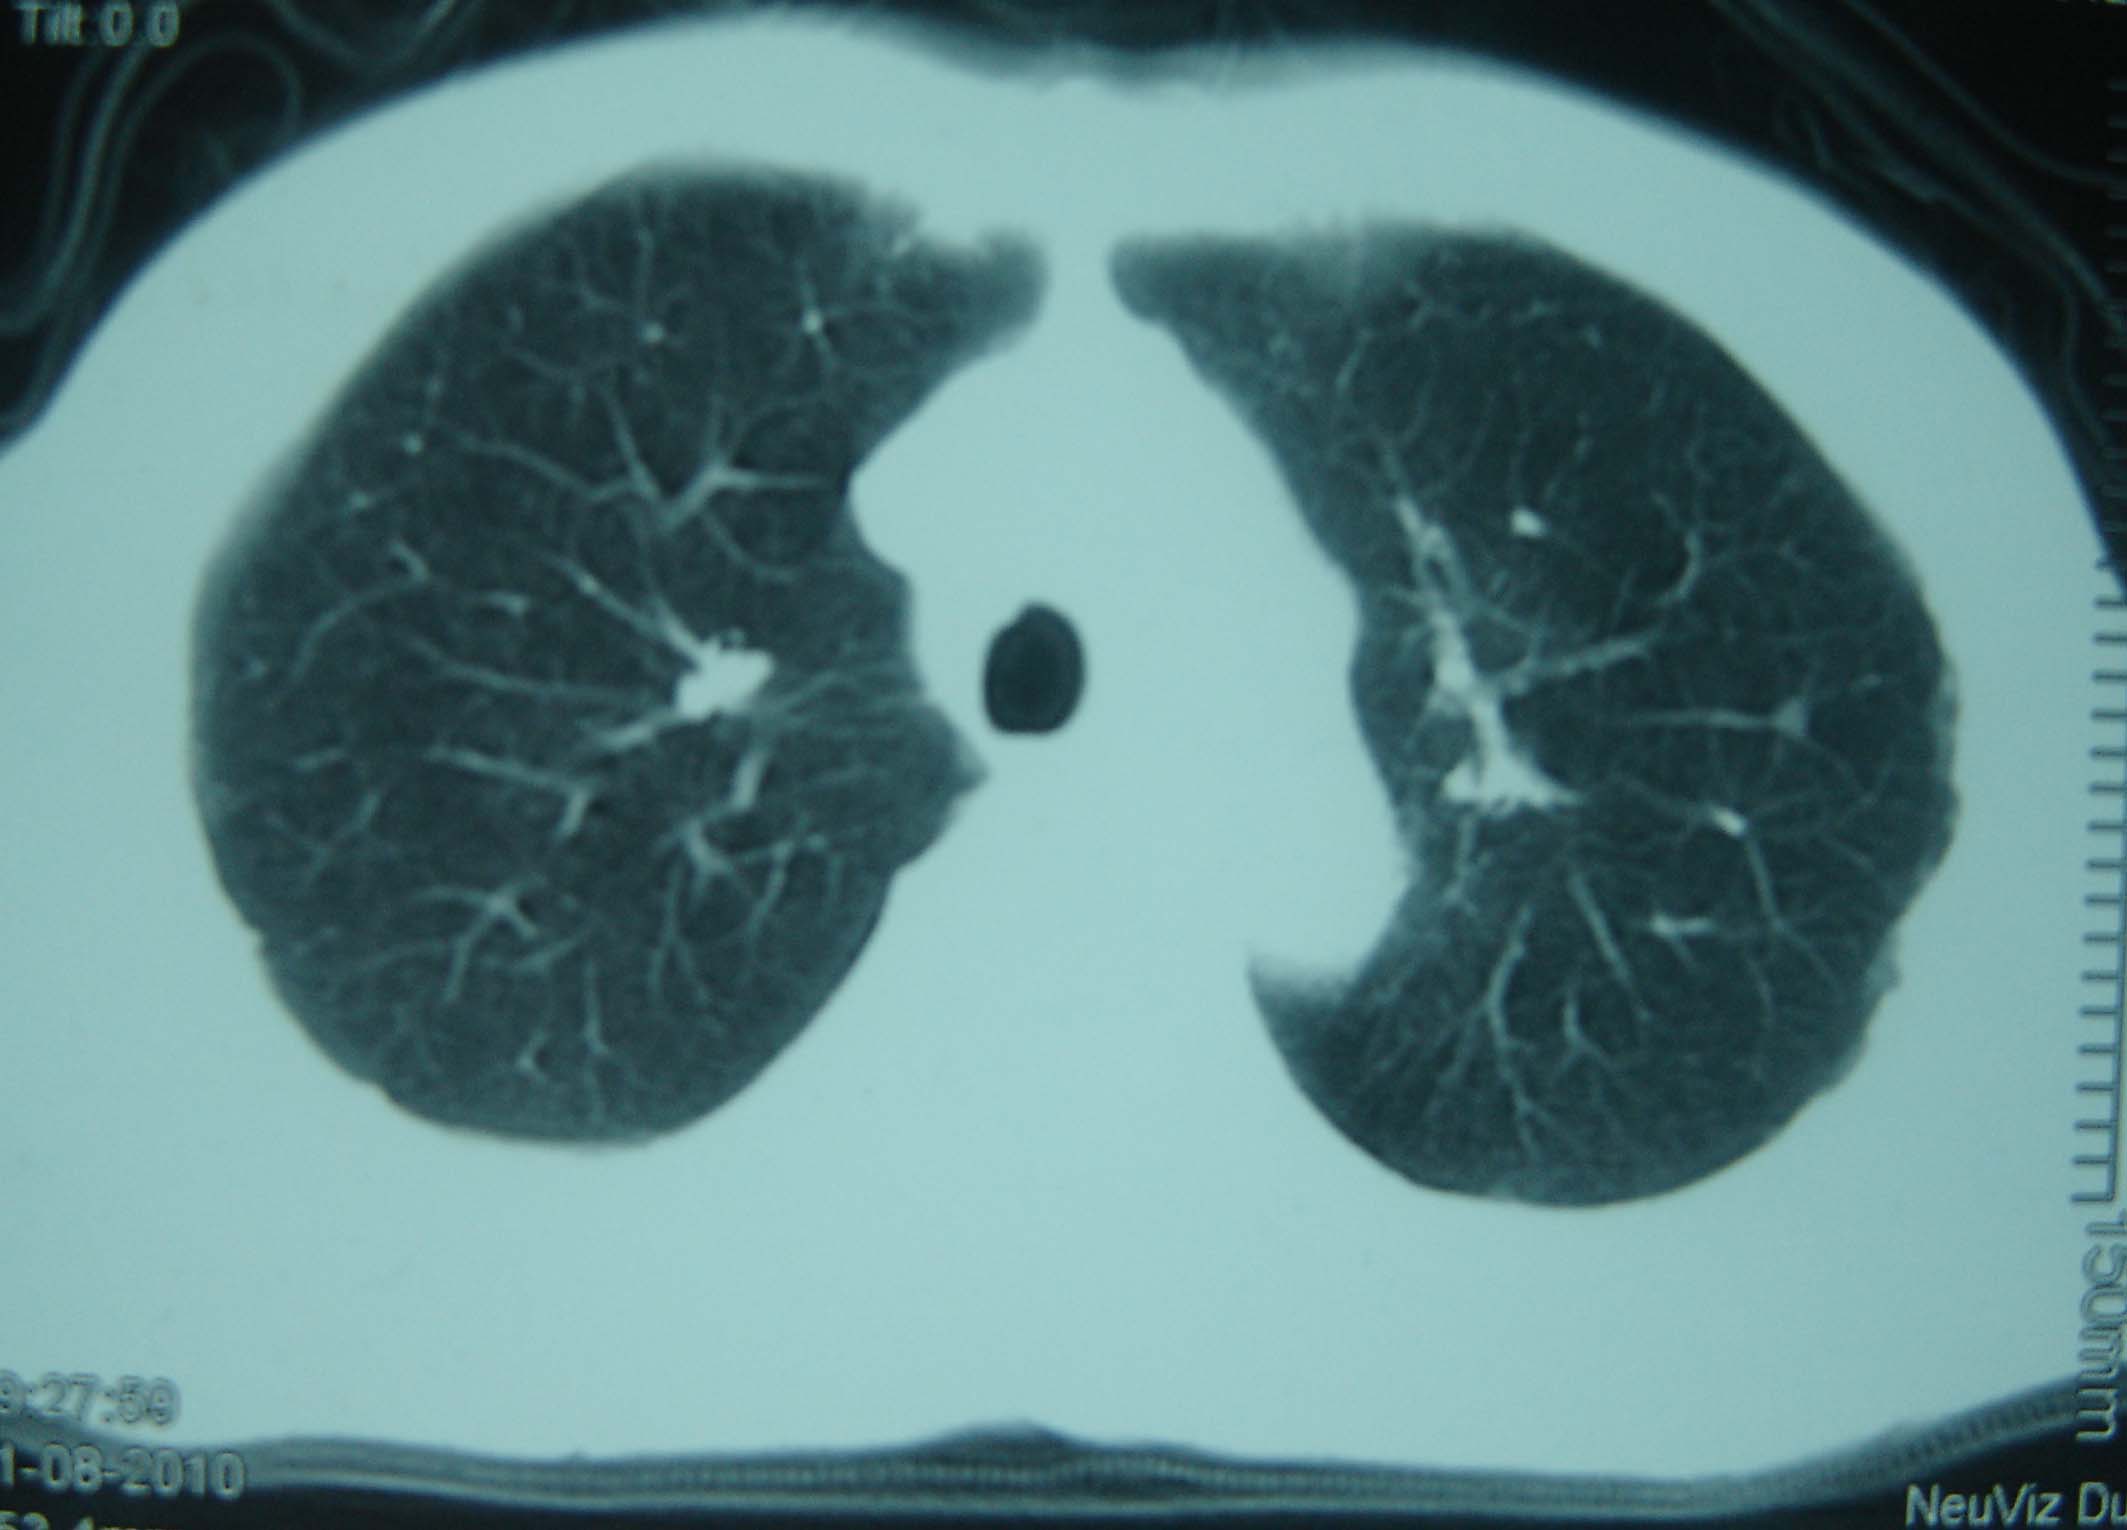

标题: CT25321:两肺多发结节 请会诊 [打印本页]

男 、43岁,咳嗽胸痛,装修工,平时接触粉尘较多,有吸烟史10多年,纤维支气管镜检查未发现异常,胃镜、腹部b超检查亦未发现异常,颈部淋巴结活检未发现肿瘤细胞。